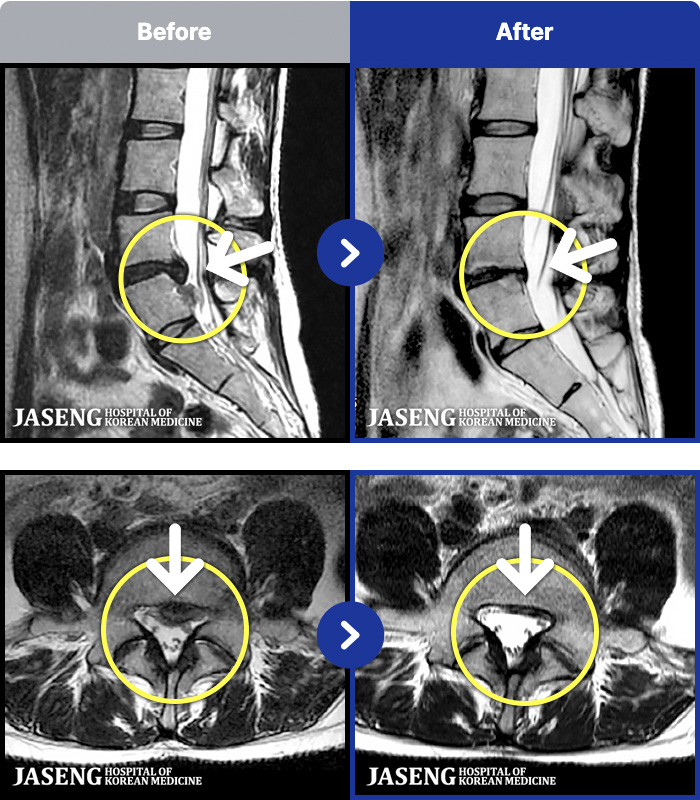

- MRI ġ

MRI ġ

191 MRI ũ ʸ Ȯϼ.

Ƹ ϰ ־.

ȯںп Ǹ ǿ ԿǾ, ο ġ ۿ Ƿ ġḦ Ͻñ ٶϴ.